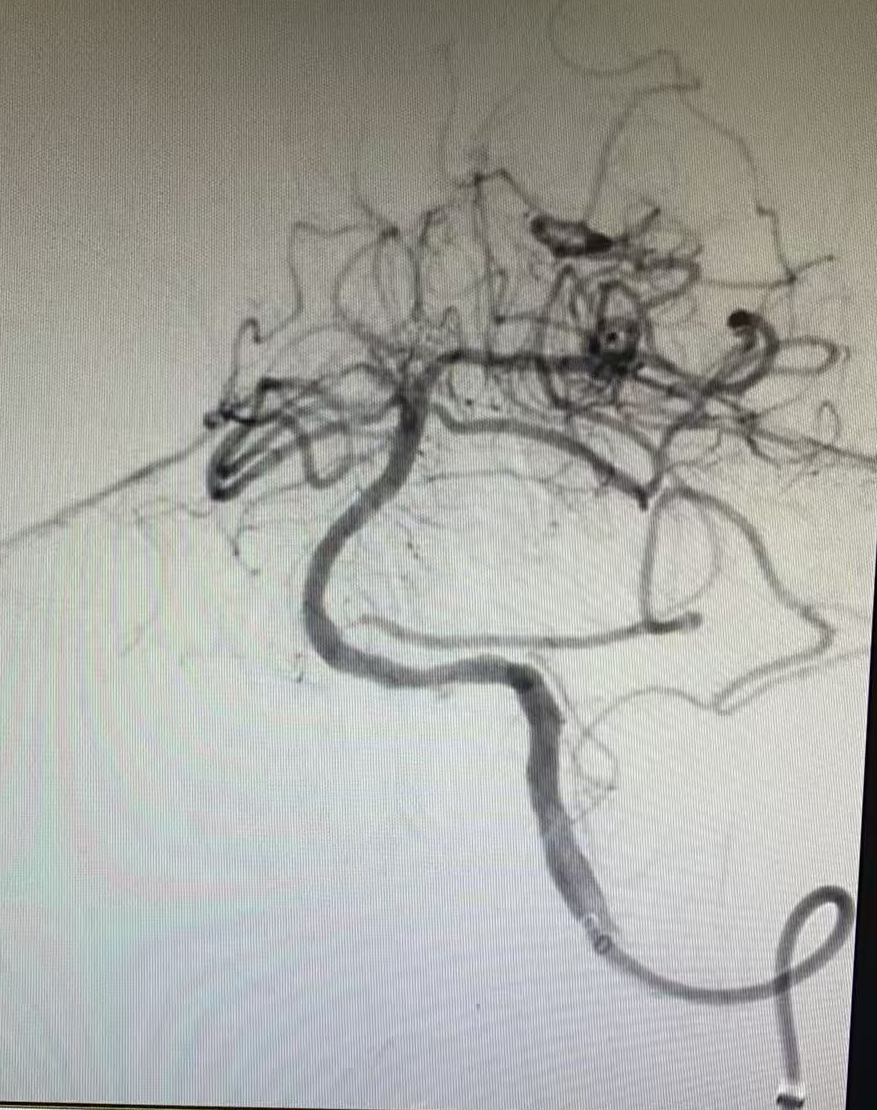

但挑戰(zhàn)還在繼續(xù),血管開通后發(fā)現(xiàn)內(nèi)部存在嚴(yán)重狹窄,遠(yuǎn)端血流灌注不足,團(tuán)隊(duì)隨即進(jìn)行球囊擴(kuò)張改善血流,但血管回縮明顯。為確保持久通暢,團(tuán)隊(duì)果斷植入一枚支架。最終,血管形態(tài)恢復(fù)良好,血流達(dá)到最佳標(biāo)準(zhǔn),缺血的大腦獲得了充足的血液供應(yīng)。

支架置入后

一場(chǎng)集腦動(dòng)脈造影、顱內(nèi)動(dòng)脈取栓、球囊擴(kuò)張與支架置入于一體的多模態(tài)手術(shù)順利完成。